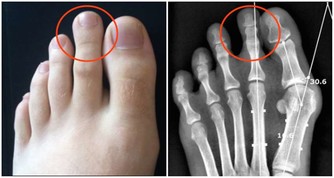

1.杵狀指

當你身體的含氧量太低,就可能會出現杵狀指。

指甲的底部和周邊呈現隆起的曲線。

這是心血管疾病或肺部腫瘤的指標。